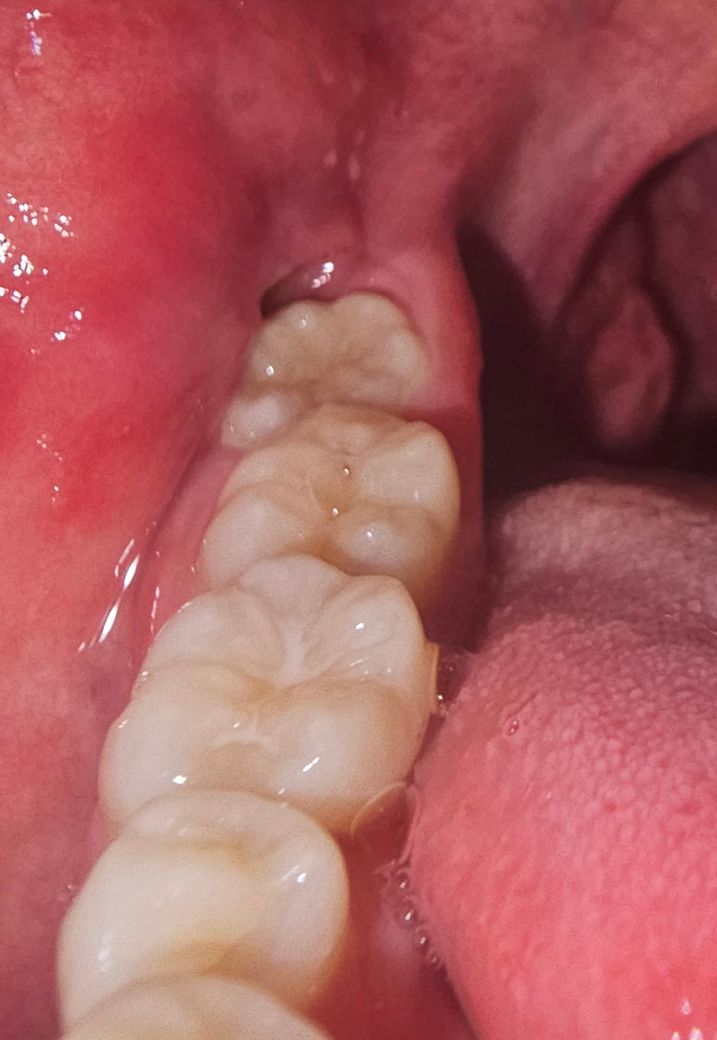

사진속의 잇몸 염증질문 탄툼으로 연명중

지난주에 항생제 3일먹고

이번주는 탄툼으로 연명하고 있는데

자연치유가능이나 다른 시술가능한지 문의합니다

발치는 전에 대학병원에서 폰빌레브란트병 의심으로

몇년 진료받은적이 있어서 그냥 치과에선 발치를 못하고 시간이 걸립니다

• 1번 째 사진

사랑니 때문에 염증이 생겨서 불편한거 같습니다. 계속 불편하시면 사랑니 발치를 하시는게 좋을것같습니다.

사랑니로 인해서 잇몸에 염증을 유발한다면 사랑니를 발치해주는 것이 좋습니다. 지속적으로 염증을 유발하게 되면 주변 조직에 손상이 발생할 수 있기 때문입니다